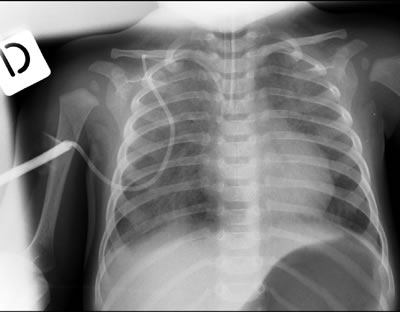

Il quadro che ci appare (Figura 1) è quello di un polmone “sporco” come da polmonite interstiziale.

Il sospetto è che il bambino possa avere una polmonite interstiziale o da virus o da Pneumocisti carinii. La diagnosi di polmonite da Pneumocisti carinii viene confermata il giorno seguente dalla ricerca biologica su aspirato (PCR positiva). Gli esami avviati per la ricerca di altri possibili agenti eziologici di polmonite interstiziale in immunodepresso (CMV, virus parainfluenzali) arriveranno nei giorni seguenti, e sono negativi.

L’esecuzione di una lastra del torace può mettere in luce il quadro di polmonite interstiziale caratteristico, prima che la malattia si renda clinicamente più evidente, e suggerendo da subito il trattamento antibiotico adeguato.

Inizialmente l’RX può essere normale (come nel nostro caso). In seguito possono comparire infiltrati interstiziali peri-ilari, con progressione verso la periferia. Il quadro può progredire con consolidamento degli spazi aerei (alveolari) bilaterali, mimando un edema polmonare, ma con risparmio degli spazi costo-frenici e degli apici.